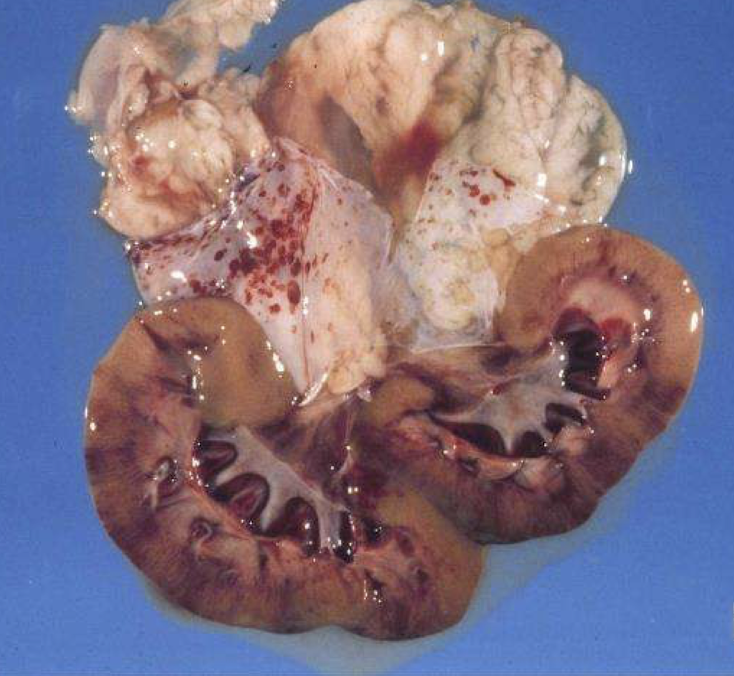

What complications are shown in the necropsy images related to urinary obstruction?

Marked hydronephrosis

Hydroureter

Severe bladder distention

Consequences of prolonged obstruction → pressure atrophy and renal damage

What does hydronephrosis look like grossly?

Dilated renal pelvis

Thinned cortex

Progressive pressure atrophy

no room to expand due to the fixed cortex, fluid accumulates in the kidney. kidney does not have a shut off system and will continue producing urine

What is the pathophysiology of hydronephrosis?

Capsule is non-expansile

Obstruction → ↑ intrarenal pressure

Lymphatics & veins obstruct → ↓ blood flow → hypoxia

Results in pressure atrophy and apoptosis of renal cells